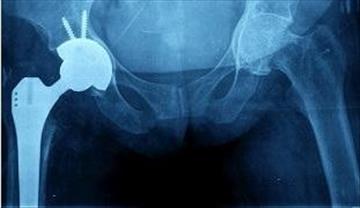

Diz veya kalça implantları ve işitme cihazları gibi bazı tıbbi bileşenler için, bileşenin yerleşik şekli hızlı hasta iyileşmesi ve maksimum konfor için çok önemlidir. Dijital bir lazer tarayıcı kullanarak hastaya özgü bir parçayı sayısallaştırarak, tüm geometri grafik renk şemaları temelinde değerlendirilebilir.